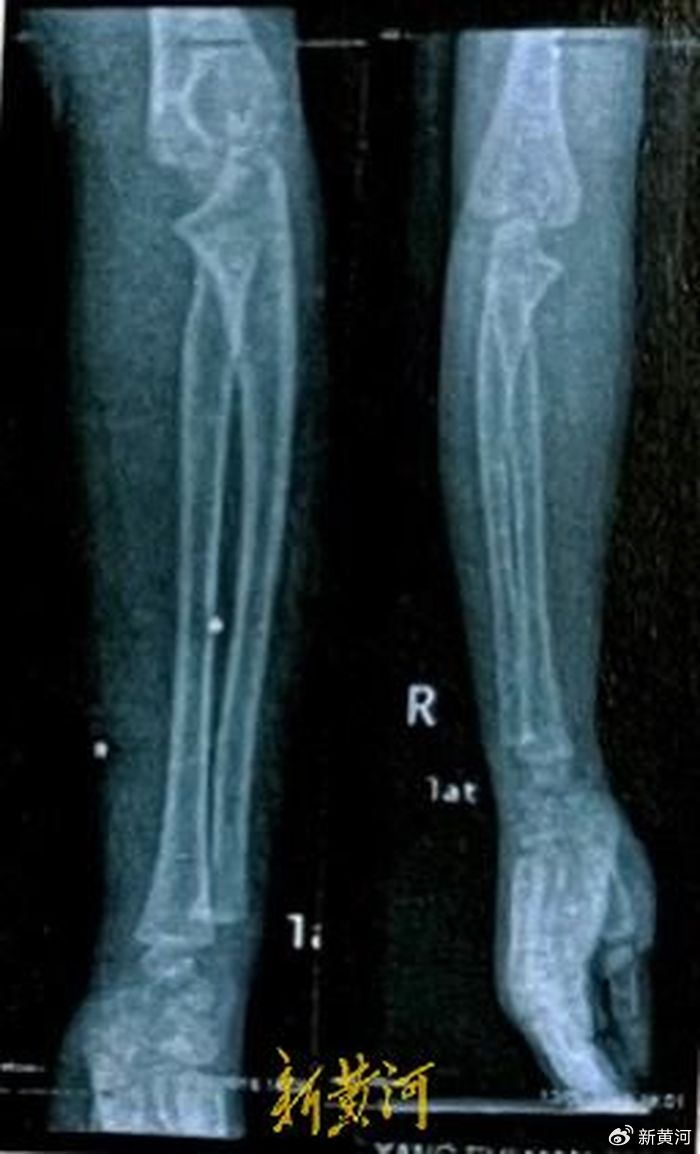

回忆起妹妹受伤的那天,晓辉依旧记忆深刻。“当时,妹妹全身都是血,整个人都昏迷了,且四肢抽搐,后背满是中弹痕迹。事情发生后,家人先后带着妹妹去了砚山县医院、文山州医院,后又转到了昆明市儿童医院等进行抢救。”晓辉回忆说,当时在昆明市儿童医院拍摄的CT显示,晓彤全身共有27颗铁砂弹片:右耳后1处、枕部3处,左肺下叶、T12椎管内、右肾、膀胱内、右侧大腿及小腿等都有高密度金属病灶。“其中最严重的是颅骨与脊椎处的铁砂,急需手术取出。”晓辉说,2016年1月25日,晓彤进行了颅骨、颅内手术,2月1日,又进行了脊椎手术,前后共取出4颗弹片。

剩余的23颗,医生担心晓彤年纪太小,且手术风险高,如继续手术可能会造成更大损伤,只能选择先观察,等休养好再进行手术。